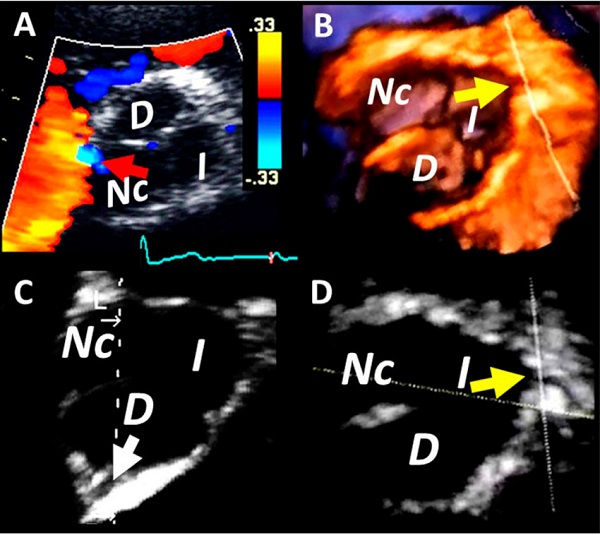

En el ETT 2D desde vistas apicales observamos una imagen con las características de TRAC. En el eje corto paraesternal izquierdo color se visualizó un flujo sistodiastólico de baja velocidad, cercano a la comisura entre el seno derecho y no coronariano (Figura 1A, no se pudo obtener señal espectral).

Se decidió completar el estudio con ecocardiograma transtorácico 3D (ETT 3D). Se midió el volumen de la raíz aórtica (Figura 1B) y en el análisis de reconstrucción multiplanar se pudo visualizar el origen normal de la arteria coronaria derecha (Figura 1C, flecha blanca) e izquierda (Figura 1B, D, flecha amarilla) desde sus respectivos senos de Valsalva. Con estos datos presumimos que la arteria con trayecto retro aórtico sería la arteria Cx.